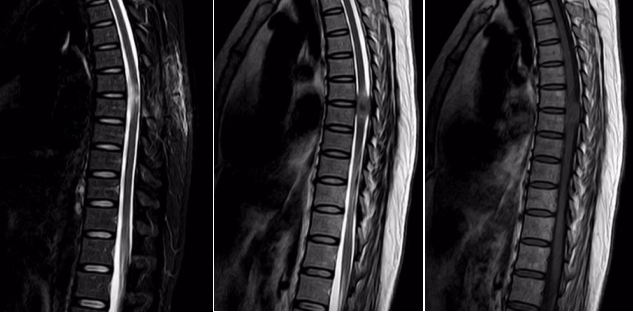

一位女性患者,11个月前没有明显诱因出现双下肢麻木、无力症状,同时伴有排便无力和间歇性跛行的情况,当时并未引起重视。一段时间后,病情逐渐加重,10天前竟严重到无法行走。为寻求治疗,患者来到我院脑外科就诊。门诊通过胸椎 MRI+增强检查发现,胸6-7椎管内左缘髓外硬膜下富血供肿瘤,再结合CT检查后,考虑脊膜瘤,于是以“椎管内占位性病变”将患者收入脑外科住院治疗。

入院后,脑外科团队积极开展术前准备工作。经过详细诊断,基本确定为椎管内肿瘤,脊膜瘤的可能性最大,决定为患者实施肿瘤切除术。术中可见肿瘤呈砂砾状,大小约1.5×2.2cm,颜色呈灰白色,血供丰富且质地坚韧,相应位置的硬脊膜增厚,脊髓受压明显且向右移位,不过幸运的是,肿瘤与脊髓并无明显粘连。在显微镜下,医护人员小心翼翼地将肿瘤分离,严密保护脊髓,最终分块将肿瘤完全切除,病理诊断结果为脊膜瘤。患者恢复良好,现已顺利出院。